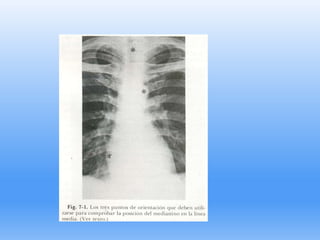

TRAUMA DE TÓRAX

Diagnóstico radiológico

Tamaño del neumotórax

Teniendo en cuanta el principio

de que el volumen del pulmón

y el hemitórax son Aproximadamente

proporcionales al cubo de sus diámetros

el tamaño del neumotórax

Puede ser calculado a partir de la

relación del diámetro del pulmón

elevado al cubo sobre el diámetro del

Hemitórax elevado al cubo , expresado

como porcentaje.